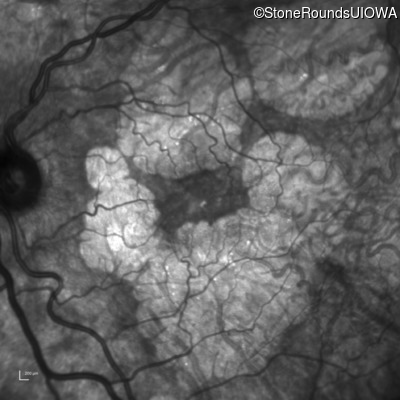

AR Stargardt Disease (IIA)

Age at visit: 51 years

This 51 year old woman first experienced some abnormality in her distance vision when she was 27 years old. She feels that her vision has been stable since that time.

Diagnosis & molecular findings

Disease Gene Allele 1 variant(s) Allele 2 variant(s) Inheritance mode

AR Stargardt Disease ABCA4 Gly1507Arg GGG>AGG IVS42+1 G>A AR